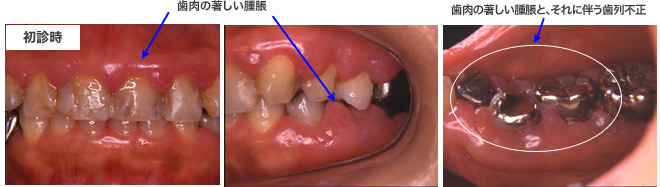

症例2:薬剤の関与が疑われる中等度歯周炎患者の治療例

- 患者

- 61歳、女性

- 診断

- 薬剤の関与が疑われる成人性歯周炎

- 所見

- 全顎的に歯肉の増殖がある。特に左側下顎臼歯部は、歯冠を覆うほどの歯肉増殖がある。レントゲンでは、全顎的に水平的な骨吸収がある。また小臼歯部に垂直性の骨吸収がある。

- 治療方針

- 患者は、降圧剤、抗ヒスタミン薬を服用しており、このことが歯肉の増殖に関与していると考えたため、内科医と相談のもと、服用薬の変更、減量を行う。また、歯肉縁下の感染源の除去を行うとともに、局所的に炎症を助長させる局所要因を改善すること。

- 治療計画

- 薬剤の変更・減量

歯周初期治療(TBI、SRP、不良補綴物の再製)

歯周外科処置(左下臼歯部、上顎左右臼歯部)

MTM(左下臼歯部)

メインテナンス(SPT)

初診時にあった、歯を覆い隠さんばかりの歯肉の腫脹は、歯周治療と薬剤の減量・交換によってなくなりました。上下の写真を見比べたら、初診時にどれほど歯肉が腫脹していたか良く分かると思います。歯周治療が終わり、メインテナンスに移行した現在も、歯肉が腫脹することはなく、良好な経過をたどっています。